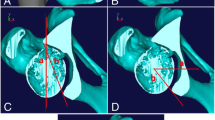

In the first phase, a DICOM format file from a pre-operative CT scan is uploaded into a medical software application (EBS, Ekliptik, d.o.o., Ljubljana, Slovenia) where a virtual 3D model of the pelvis and the hips is generated (Video 1). The surgeon and the software specialist plan the bone cuts and determine the desired acetabular fragment position and orientation on a 3D virtual pelvic model (Fig. 2, Video 1) taking into consideration also the virtual pre-operative hip range of motion (ROM) trial estimates to avoid any potential impingement. We also design the PST congruent to the exposed bones with holes for guidance of the Kirschner wires along with the planned posterior acetabular cut and a plane for the guidance of the superior iliac cut (Video 1).

The third phase is the surgery. The patient is lying supine on the radiolucent operating table. The skin incision starts in the inguinal fold extending approximately 2 cm below the anterior superior iliac spine to the middle third of the iliac crest. The soft tissue exposure is then continued as described by Siebenrock et al. [17]. Next, the reference sensor is carefully fixed onto the iliac crest on the Steinmann pin–like holder and the acquisition of pelvic anatomy is accomplished with the pointer (Video 1). The accuracy of the acquisition is then checked and rechecked with the pointer and navigated chisel. The surgery continues with the execution of ischial osteotomy, performed through infra-articular space as described by Siebenrock et al. [17], with the help of navigated curved osteotome (Video 1). The pubic osteotomy entry point is then marked with the navigated osteotome and finished with a straight non-navigated osteotome (Video 1). Next, we position the PST on the iliac crest, and two Kirschner wires are inserted through pre-designed holes in the template into the posterior column (Video 1). The retroacetabular osteotomy is cut along K-wires, and the superior iliac cut along the predesigned plane on the PST. In the EMN group, we position the measuring sensor onto the fragment before we mobilize it and then we navigate it to the pre-operatively planned position with the help of the EMN (Video 1, Video 2). In the XR group, its preplanned final position was determined with the help of fluoroscopy. The definitive osteosynthesis of the reoriented fragment with three 4.5-mm cortical screws was the same in both groups.

On the follow-up visit 3 months after the surgery, major complications were recorded and standing anteroposterior radiographs of hips and pelvis were performed in all patients. With the use of EBS software (Ekliptik, d.o.o., Ljubljana, Slovenia) we also created, 2D renders of hips and pelvis from the preoperative 3D models of hips and pelvis, with the virtually reoriented position of the acetabular fragment according to the planning (Fig. 4). The 2D pelvic renders were adjusted to the real post-operative radiographs of hips and pelvis (Fig. 5). The acetabular fragment position on the 2D renders (LCEA and AI) represented the basis for comparative analysis of the difference between planned and achieved LCEA and AI for both groups.